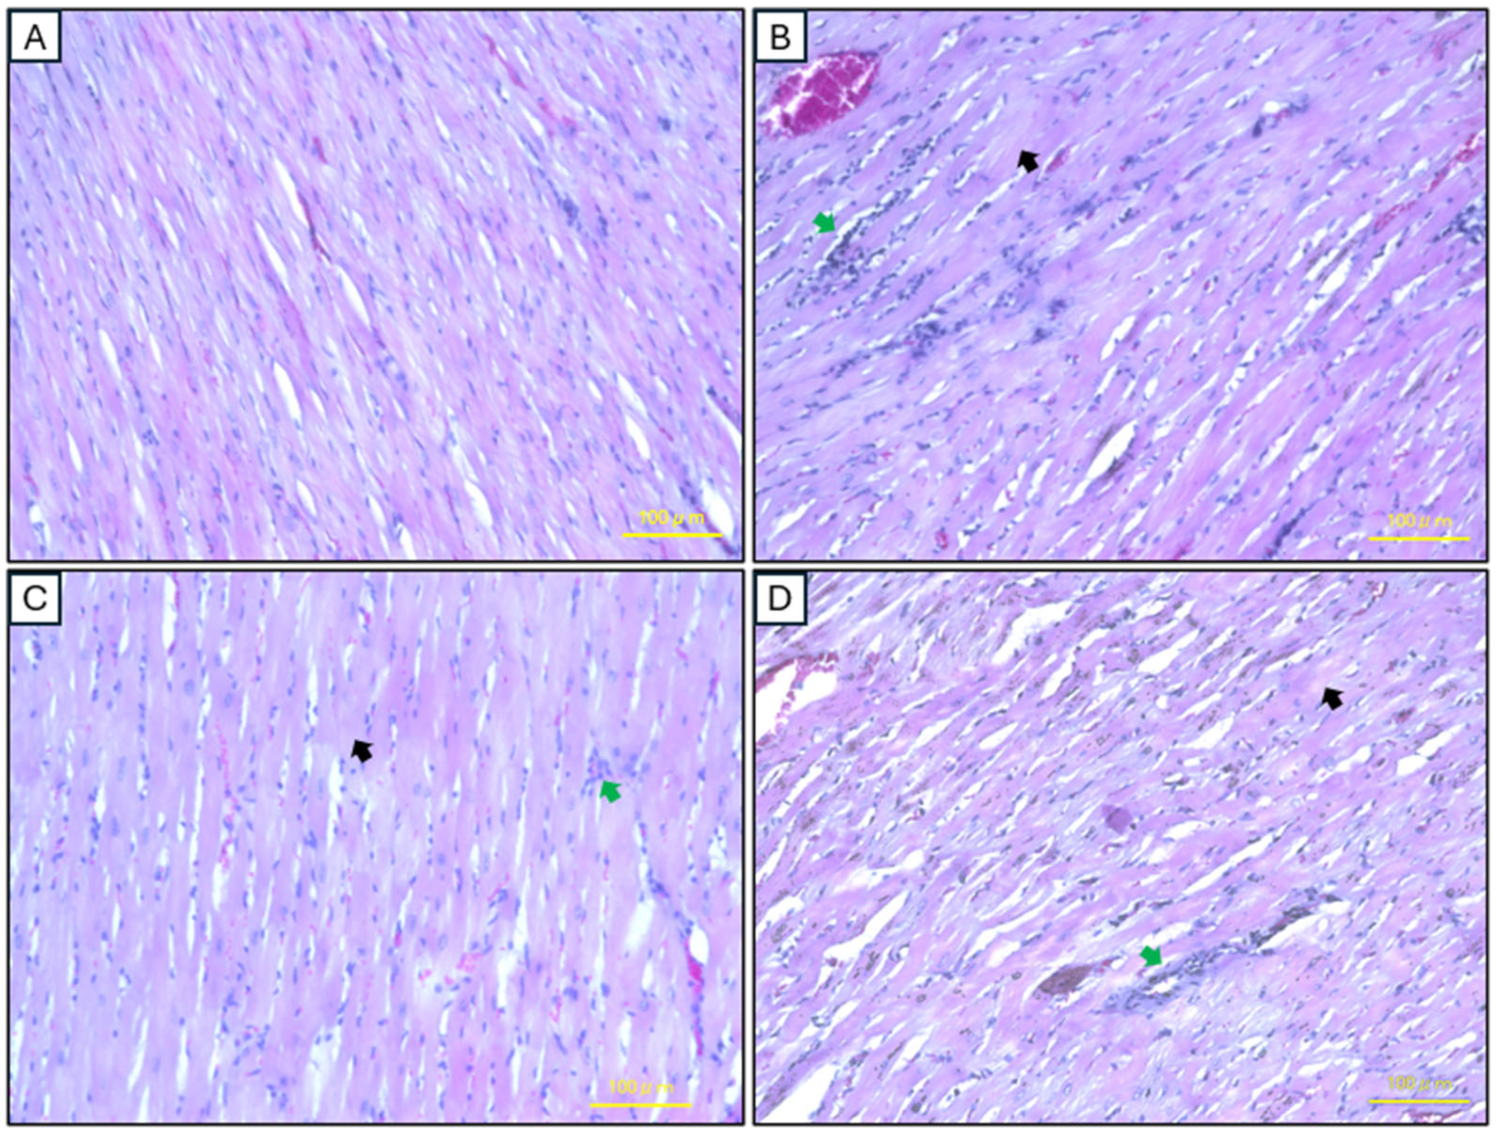

2.5. Histopathological Analysis of Cardiac Tissues

4.8.2. Cardiac Tissues

4.8.3. Staining Procedures

H&E Staining